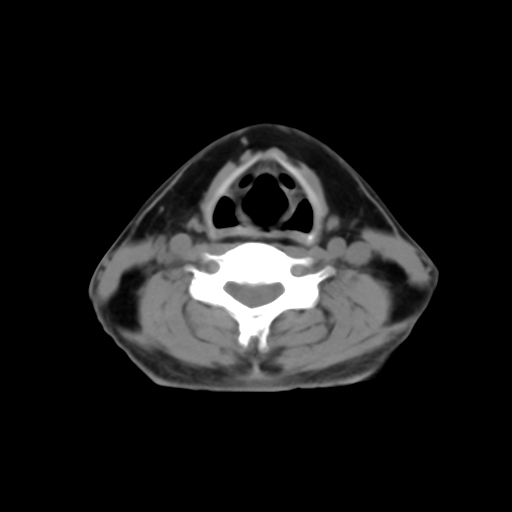

标题: CT24019:男,45岁,发现颈部肿物5个月。 [打印本页]

男,45岁,发现颈部肿物5个月,彩超示:双侧颈部及下颌部软组织增厚。

考虑双侧颈项部良性对称性脂肪增多症。